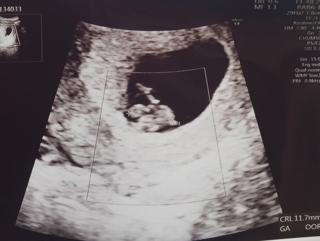

写真:7w3d:アァさん

我が子は6.6ミリで

心拍確認、お尻フリフリしていて愛らしいです